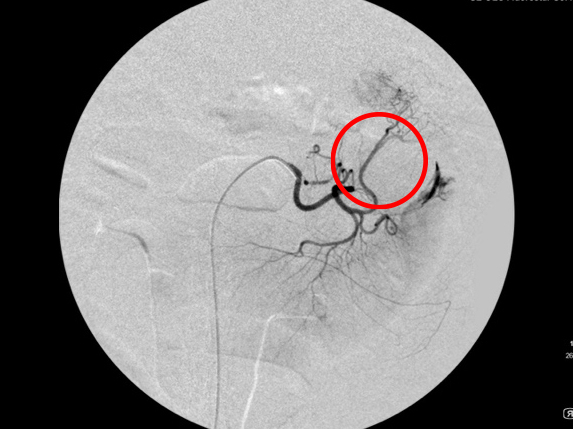

造影検査にて脾臓からの出血を確認(赤丸)